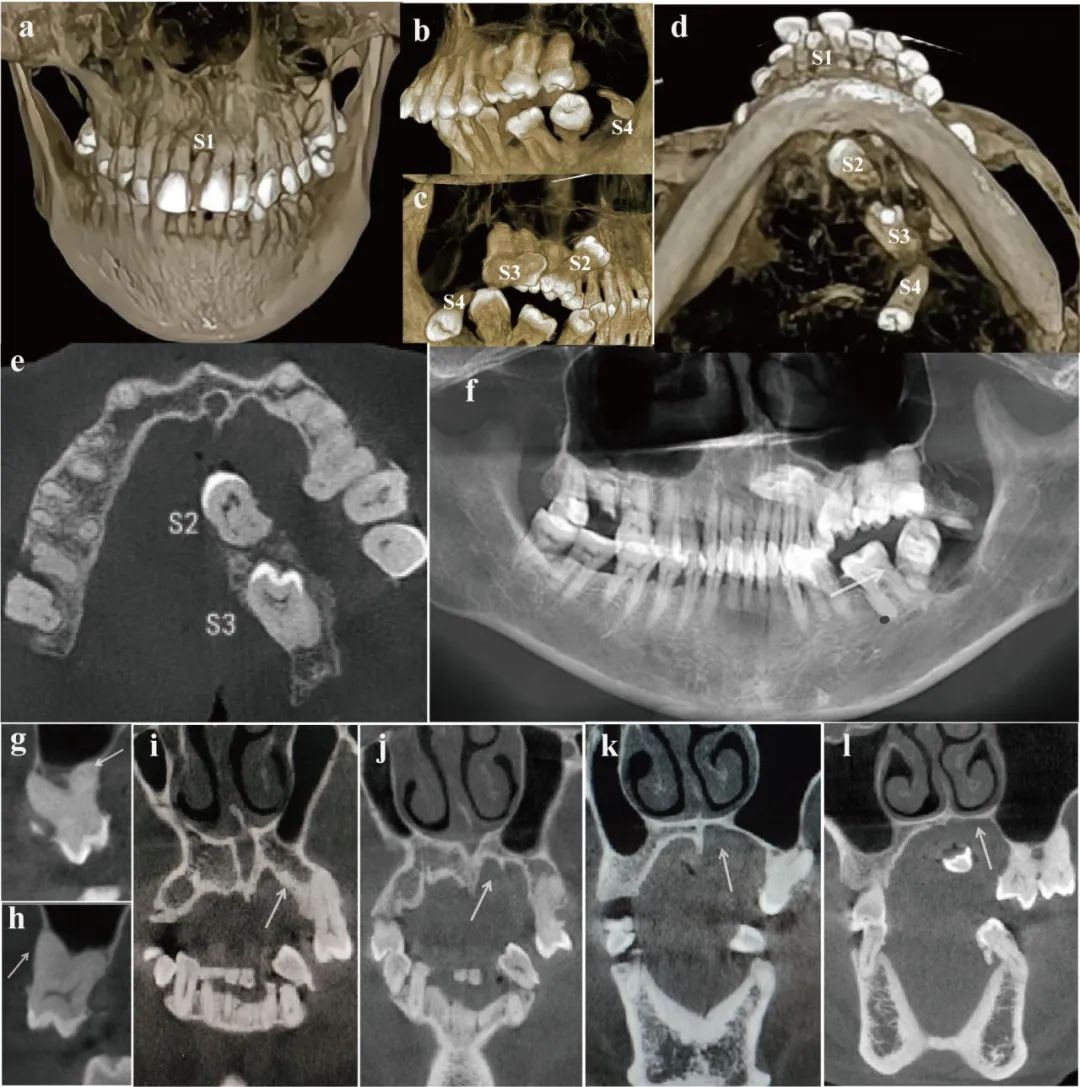

今年3月,段小红接诊了一名57岁女性患者,主诉自幼口腔左侧软组织与上腭相连,长期影响咀嚼。经过面部及全身检查后,段小红教授发现患者口腔有一条长约5厘米的异常口腔融合组织带,致使左上后牙全被遮挡,难以发挥正常咀嚼功能;进一步检查发现异常融合组织中含有一颗牙齿,并伴有局部软腭裂,正中多生牙等异常表现。

根据影像学检查显示,异常融合组织带共含有3颗多生牙,外观近似前磨牙和磨牙,其周围有骨样组织包被,且左侧硬腭骨组织厚度较右侧薄,左侧牙弓也较右侧短。由于患者的异常临床表现十分罕见,段小红教授初步判断,这可能是一种新的未曾报道过的疾病。由于观察到患者还伴有软腭裂,她一边组织团队成员翻阅大量文献,查询是否有相似病例报道,一边联合颌面整形与美容外科进行会诊。

该口腔罕见病命名为腭颊融合-腭裂-多生牙综合征。(空军军医大学口腔医院供图)